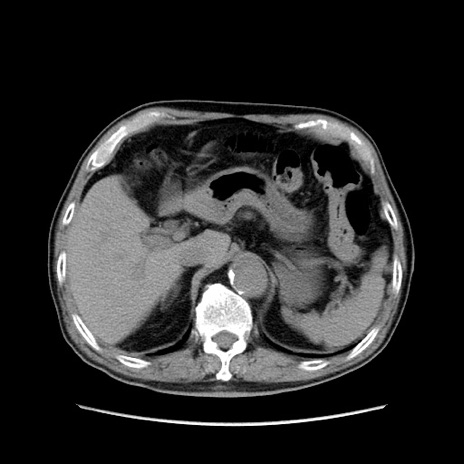

症例24(横断像)

【症例】80歳代男性

【主訴】左側腹部痛、嘔吐

【現病歴】本日早朝より左腹部に痛みあり。昼頃嘔吐認めたため、救急要請。

【既往歴】直腸癌(Mile手術)、胆摘

【身体所見】意識清明、BT 35.9℃、BP 221/93mmHg、SpO2 97%(RA) 、腹部:左ストーマ周囲に限局性の腹部膨隆あり。 膨隆部自発痛・圧痛あり・軟。

【データ】WBC 7700、CRP 0.09